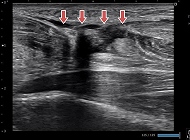

前距腓靱帯損傷

レントゲンでは評価できない靭帯損傷の有無、ゆるみの状態がわかります。

肩腱板断裂

腱板断裂がはっきりわかります。

肋骨骨折

レントゲンでは肋骨骨折の評価は難しいですが、エコーでははっきりわかります。